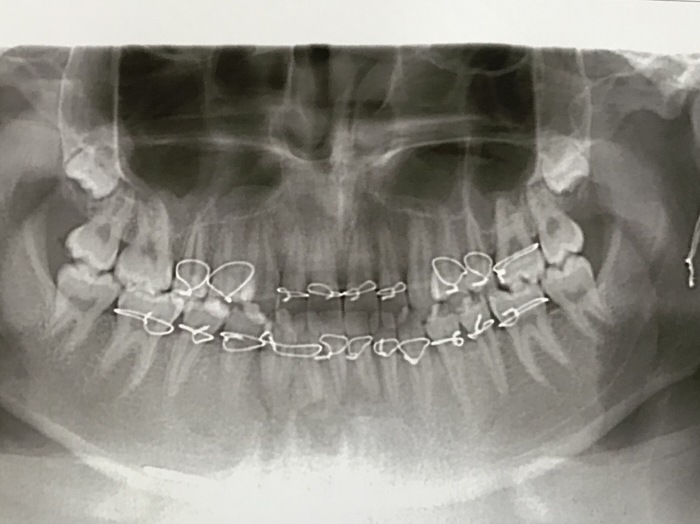

(пример правильного лечения ангулярного перелома нижней челюсти)

до лечения

после репозиции и иммобилизации отломков шинами Васильева с межчелюстной резиновой тягой

стандартная ленточная шина имени Васильева. Широкая и неудобная.

индивидуальная проволочная шина имени Тигерштедта. Обратите внимание на ее толщину и размеры

ретинированная восьмерка прямо в линии перелома

Одно движение - и нет больше восьмерки.

вид операционной раны после остеосинтеза

ортопантомограмма через 4,5 месяцев после операции остеосинтеза